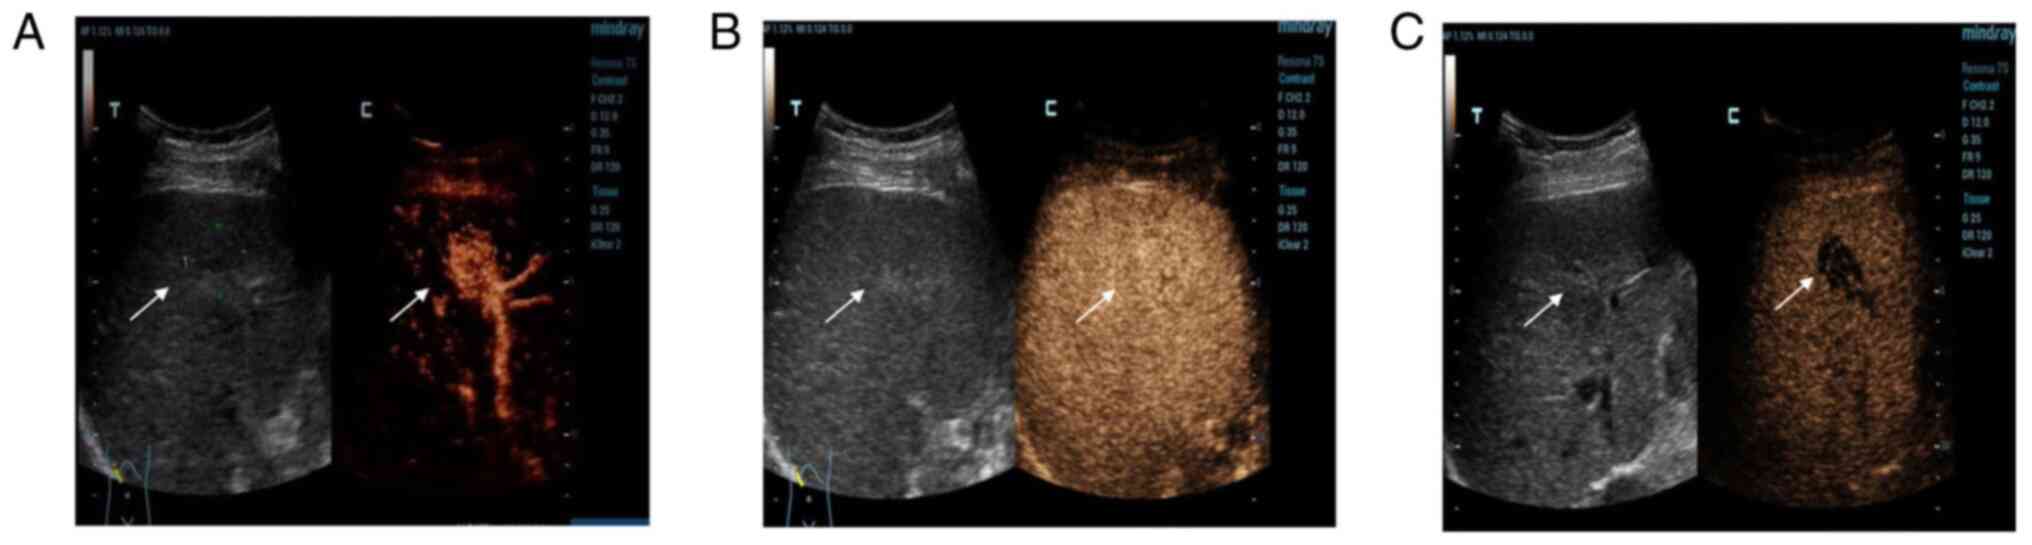

Imaging analysis of the malignant transformation of bile duct hamartomas in the liver: A case report and literature review

Bile duct hamartoma in the liver (LBDH) is relatively rare among the hepatic space‑occupying lesions that occur in adults, and the malignant transformation of LBDH is even rarer. In the present case report, a 63‑year‑old male was found to have two space‑occupying lesions in the right lobe of the liver upon ultrasound examination. Enhanced computed tomography (CT) suggested benign hepatic haemangioma, and contrast‑enhanced ultrasonography (CEUS) suggested well‑differentiated hepatocellular carcinoma. The final pathology results revealed the malignant transformation of LBDH into well‑differentiated intrahepatic cholangiocarcinoma. Improved recognition of this type of rare disease can be obtained by radiographic analysis of this case. These findings contribute to a better understanding of the enhanced development pattern of this disease on contrast‑enhanced CT, as well as on CEUS.